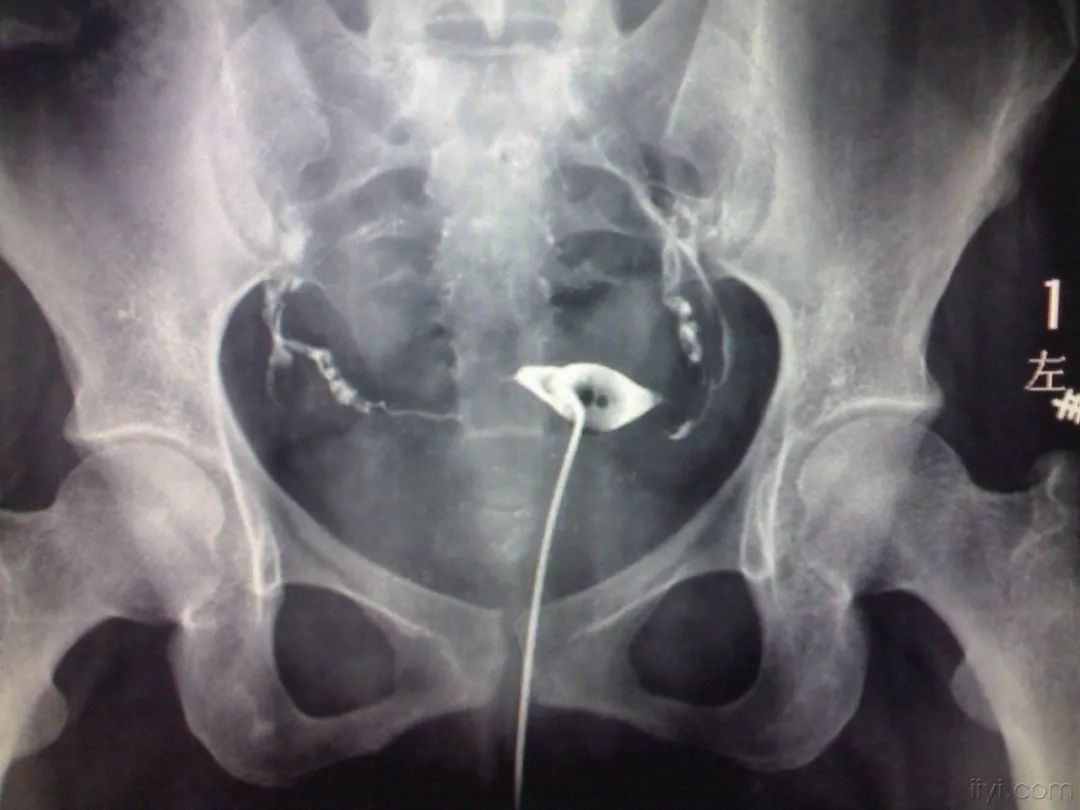

输卵管造影检查是怎么做的?

输卵管造影整个检查过程大概半个小时。医生将造影剂通过患者阴道注入宫腔,可能会觉得下腹部比较胀,但也并非传说中的十分痛苦,所以不用太担心。术后一般口服3天抗生素预防感染,2周内禁止盆浴和*生活性**。术后1周内,患者可能会出现少量阴道出血,如果没有其他不适无需就诊。如果阴道流血量多或出血时间超过一周应及时就医。